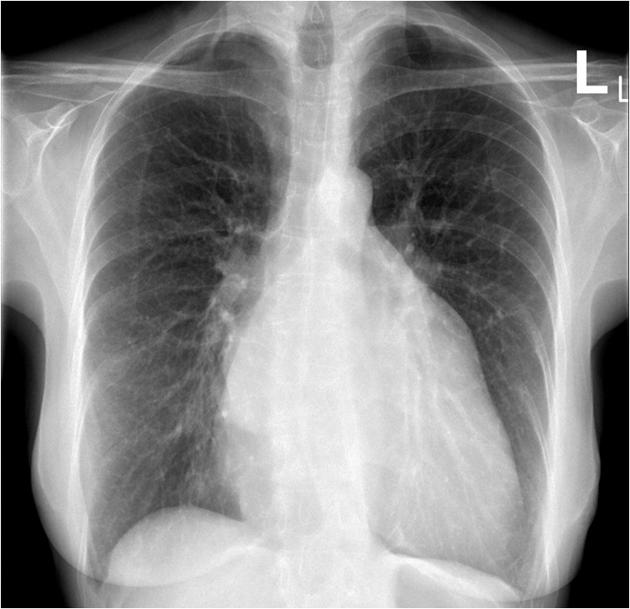

ECG: AF without acute ischemic change.CXR:CardiomegalyEchocardiogram: Severe primary (degenerative) mitral regurgitation due to mitral valve prolapses with flail P2 segment (Carpentier Type II), by integrative criteria (EROA ¡Ã0.4 cm©÷,regurgitant volume ¡Ã60 mL, vena contracta ¡Ã0.7 cm, systolic PV flow reversal,dense triangular CW jet). Baseline ECG: sinus rhythm without acuteischemic change.